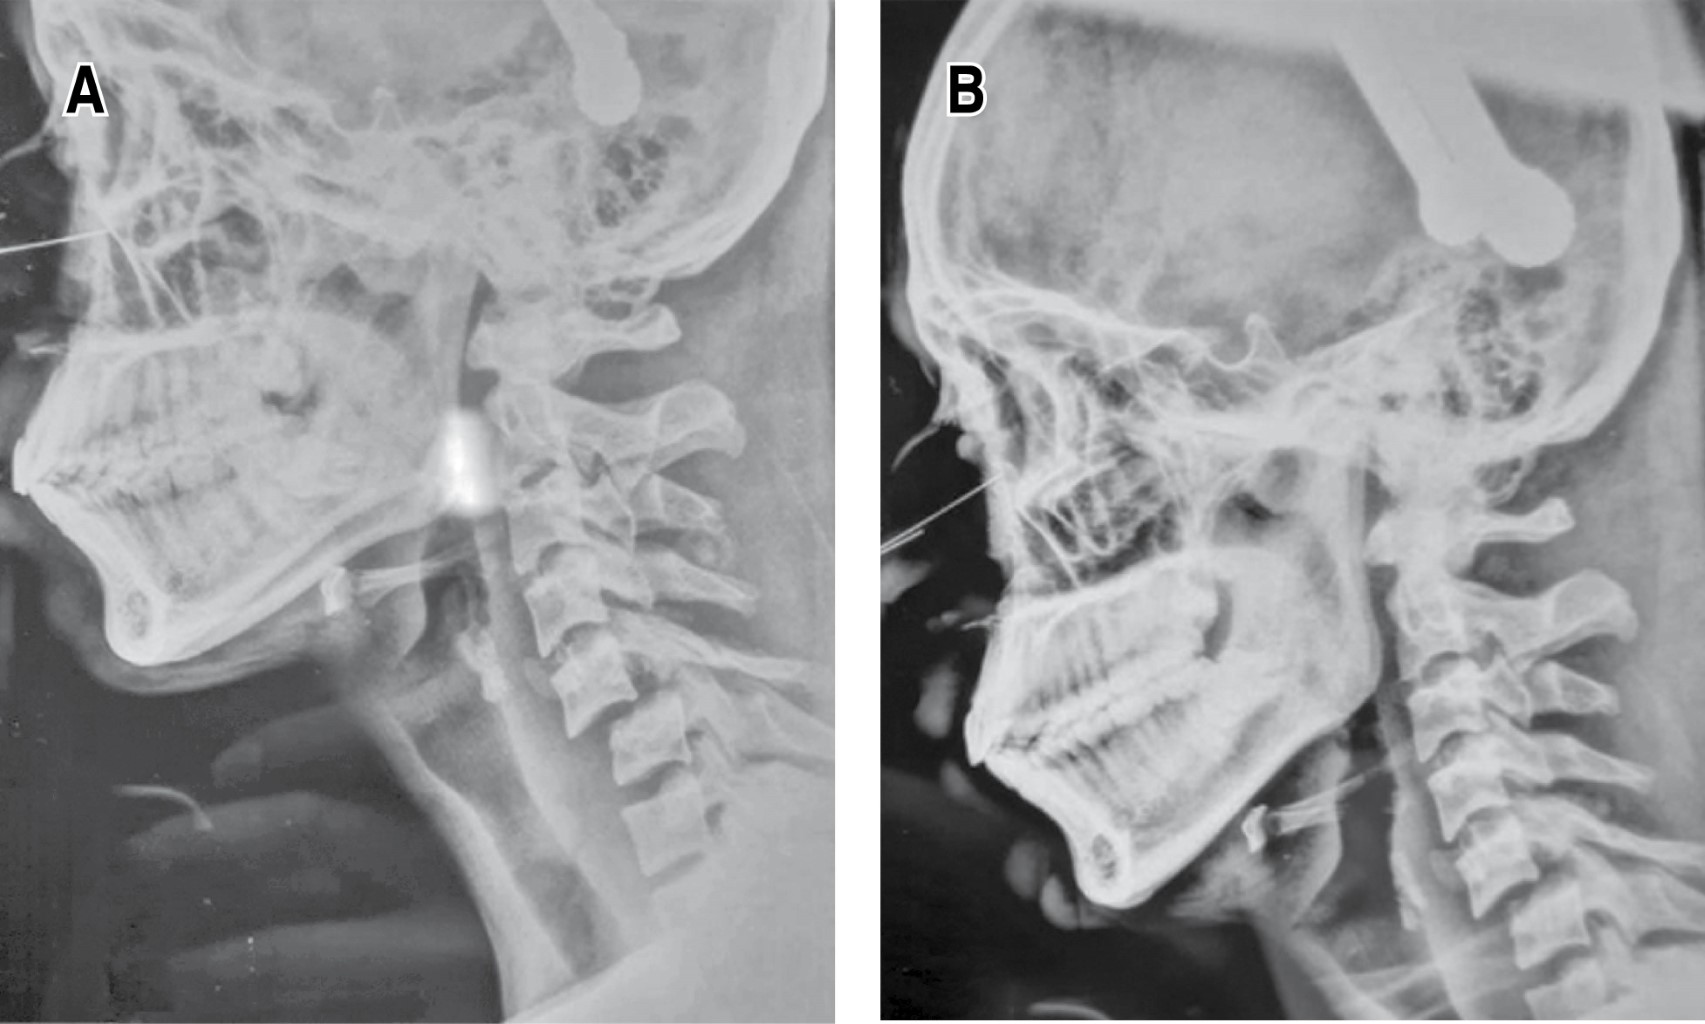

Introducción: la luxación cervical subaxial es una grave lesión, usualmente debido a un trauma de alta energía. El manejo es controvertido, más aún cuando el cuadro neurológico está intacto. Tener los estudios necesarios para evaluar el método de reducción (abierto o cerrado), así como la mejor opción de abordaje (anterior, posterior o 360°). Presentación de caso: paciente masculino de 19 años con historia de accidente de motocicleta, asistido en Hospital Regional de Petén, Guatemala. El examen neurológico evidencia función sensitiva y motora completa, radiológicamente (rayos X y tomografía) con fractura luxación C5-C6. Paciente fue inmovilizado y transferido a nuestro centro hospitalario. Al ingreso, se le realiza tracción esquelética con peso de 12 kg, con obtención de reducción parcial. Posteriormente, se realizó una instrumentación mediante abordaje posterior de C3-C7, el paciente evolucionó con adecuada función neurológica. Conclusión: el manejo de las luxaciones subaxiales sigue siendo controversial, especialmente en pacientes con un cuadro neurológico estable. La evaluación clínica adquiere un papel fundamental en centros hospitalarios sin acceso a resonancia magnética, ya que la reducción cerrada puede ser una opción efectiva siempre que se acompañe de una vigilancia neurológica continua. Asimismo, el abordaje posterior permite favorecer la cicatrización de los elementos posteriores y facilita la evaluación futura para un posible retiro del material, considerando la preservación de los discos intervertebrales.

Figura 4